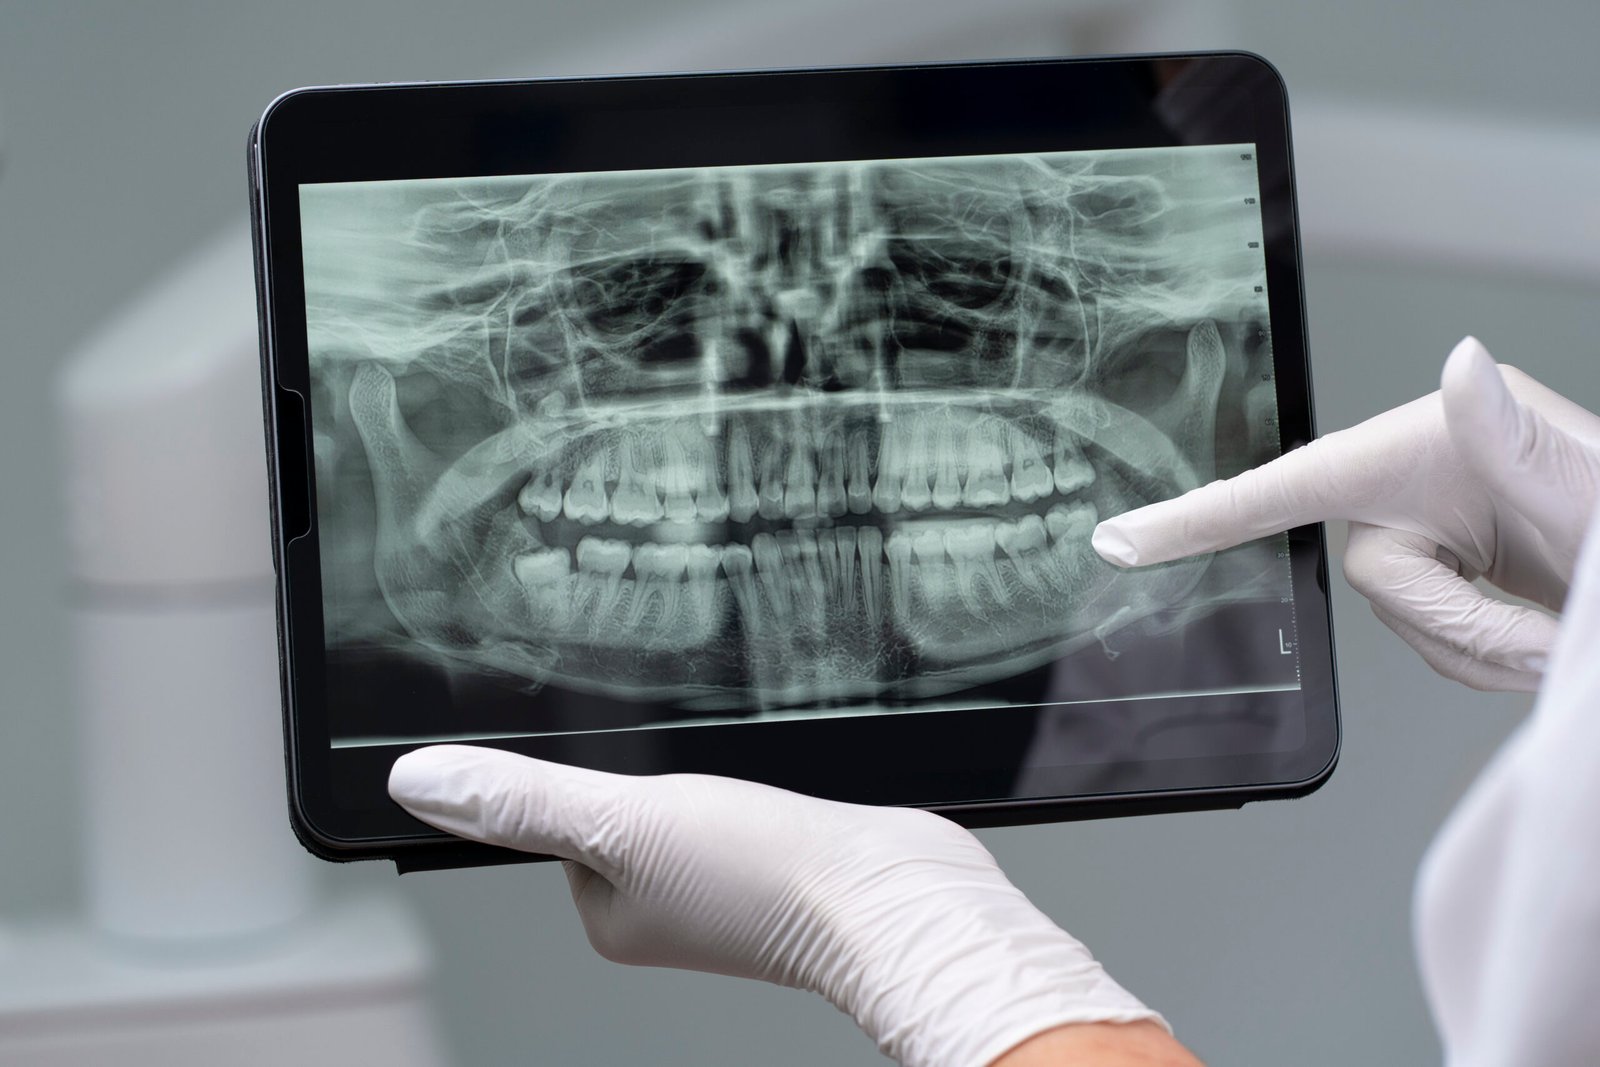

Radiografia digitală panoramică

Ortopantomografia, cunoscută și ca radiografie panoramică, oferă medicului stomatolog o vedere completă asupra dinților și a structurilor maxilo-faciale adiacente. Aceasta este recomandată înainte de orice intervenție stomatologică, permițând specialistului să analizeze în detaliu cazul. Radiografia ajută la identificarea eventualelor inflamații, a dinților incluși, a stării osului de suport, a articulațiilor temporo-mandibulare, precum și a poziției molarilor de minte. De asemenea, facilitează evaluarea relației dinților cu structuri anatomice vecine, cum ar fi nervul alveolar sau sinusurile maxilare, și detectarea posibilelor fracturi ale oaselor maxilare sau mandibulare.